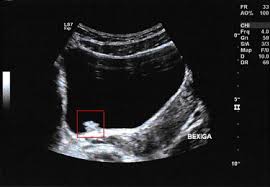

Bladder Cancer Symptoms Pictures Warning Signs Treatments Survival Rates from img.webmd.com Women have a higher chance of being diagnosed only when they have an advanced stage of bladder cancer. Bladder cancer occurs when cancerous cells, often from the lining of the bladder, begin to multiply. June 27, 2018 — a new study has found that the female bladder not only contains bacteria, but the microbes are similar to those found in the vagina. Your doctor or lab tech will only detect it with a urine. Bladder cancer is where a growth of abnormal tissue, known as a tumour, develops in the bladder lining. Find out about bladder cancer from experts at cleveland clinic. The cancer has grown through the inner lining of the bladder and into the lamina propria. These can indicate more advanced disease.

Bladder Cancer Causes Symptoms And Treatment from post.medicalnewstoday.com These can indicate more advanced disease. Males are more often affected than females. Bladder cancer is usually transitional cell (urothelial) carcinoma. Asians have the lowest rate of developing the disease. To lower the risk of bladder cancer, don't smoke and be especially careful around certain kinds of chemicals. Bladder cancer is more common in males than females. Bladder cancer is cancer that begins in the cells of the urinary bladder. Women have a higher chance of being diagnosed only when they have an advanced stage of bladder cancer.

Bladder cancer usually responds well to treatment when diagnosed early. Some of the risk factors include increased age, exposure to carcinogens. June 27, 2018 — a new study has found that the female bladder not only contains bacteria, but the microbes are similar to those found in the vagina. If you have bladder cancer, the blood eventually comes back. More caucasians than any other ethnicities seem to develop bladder cancer. Cancers of the biliary tract include cholangiocarcinoma (cancers arising from the bile duct epithelium), ampulla of vater cancer, and gallbladder cancer. Bladder cancer is characterized by the presence of blood in urine. Asians have the lowest rate of developing the disease. Bladder cancer most often begins in the cells (urothelial cells) that line the inside of your bladder. Bladder cancer is a major public health problem worldwide, with relatively high morbidity. Your doctor or lab tech will only detect it with a urine. It affects people who are older generally, but in some occurrences, younger people also have been some females get affected with prolapsed bladder also called the cystocele. Bladder cancer has long been considered a disease of older men.